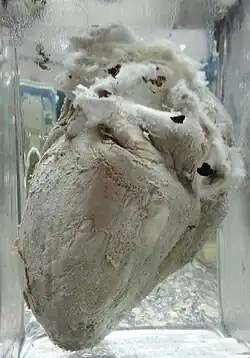

The definitive treatment for constrictive pericarditis is pericardial stripping, which is a surgical procedure where the entire pericardium is peeled away from the heart. This procedure has significant risk involved,[14] with mortality rates of 6% or higher in major referral centers.[15]

A poor outcome is almost always the result after a pericardiectomy is performed for constrictive pericarditis whose origin was radiation-induced, further some patients may develop heart failure post-operatively.[16]